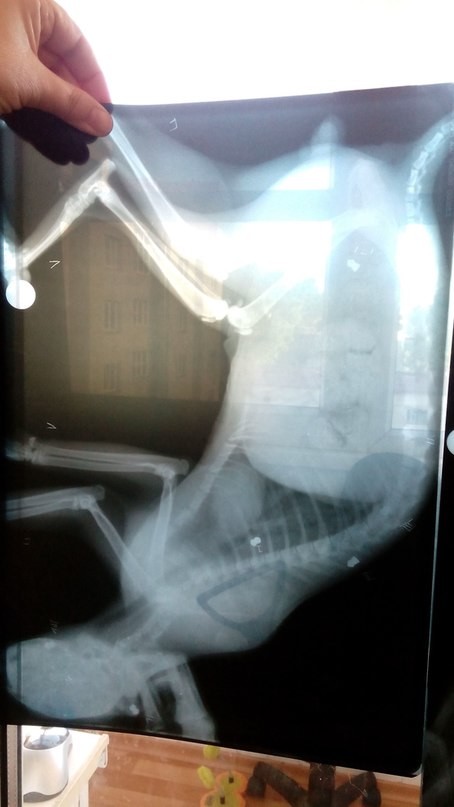

"В теле котёнка было обнаружено 9 пуль. Но, несмотря на боль, кот смог доползти к частному дому за помощью, где его подобрали неравнодушные люди. Сегодня коту будет проведена операция, которая решит его судьбу", — пояснила Екатерина